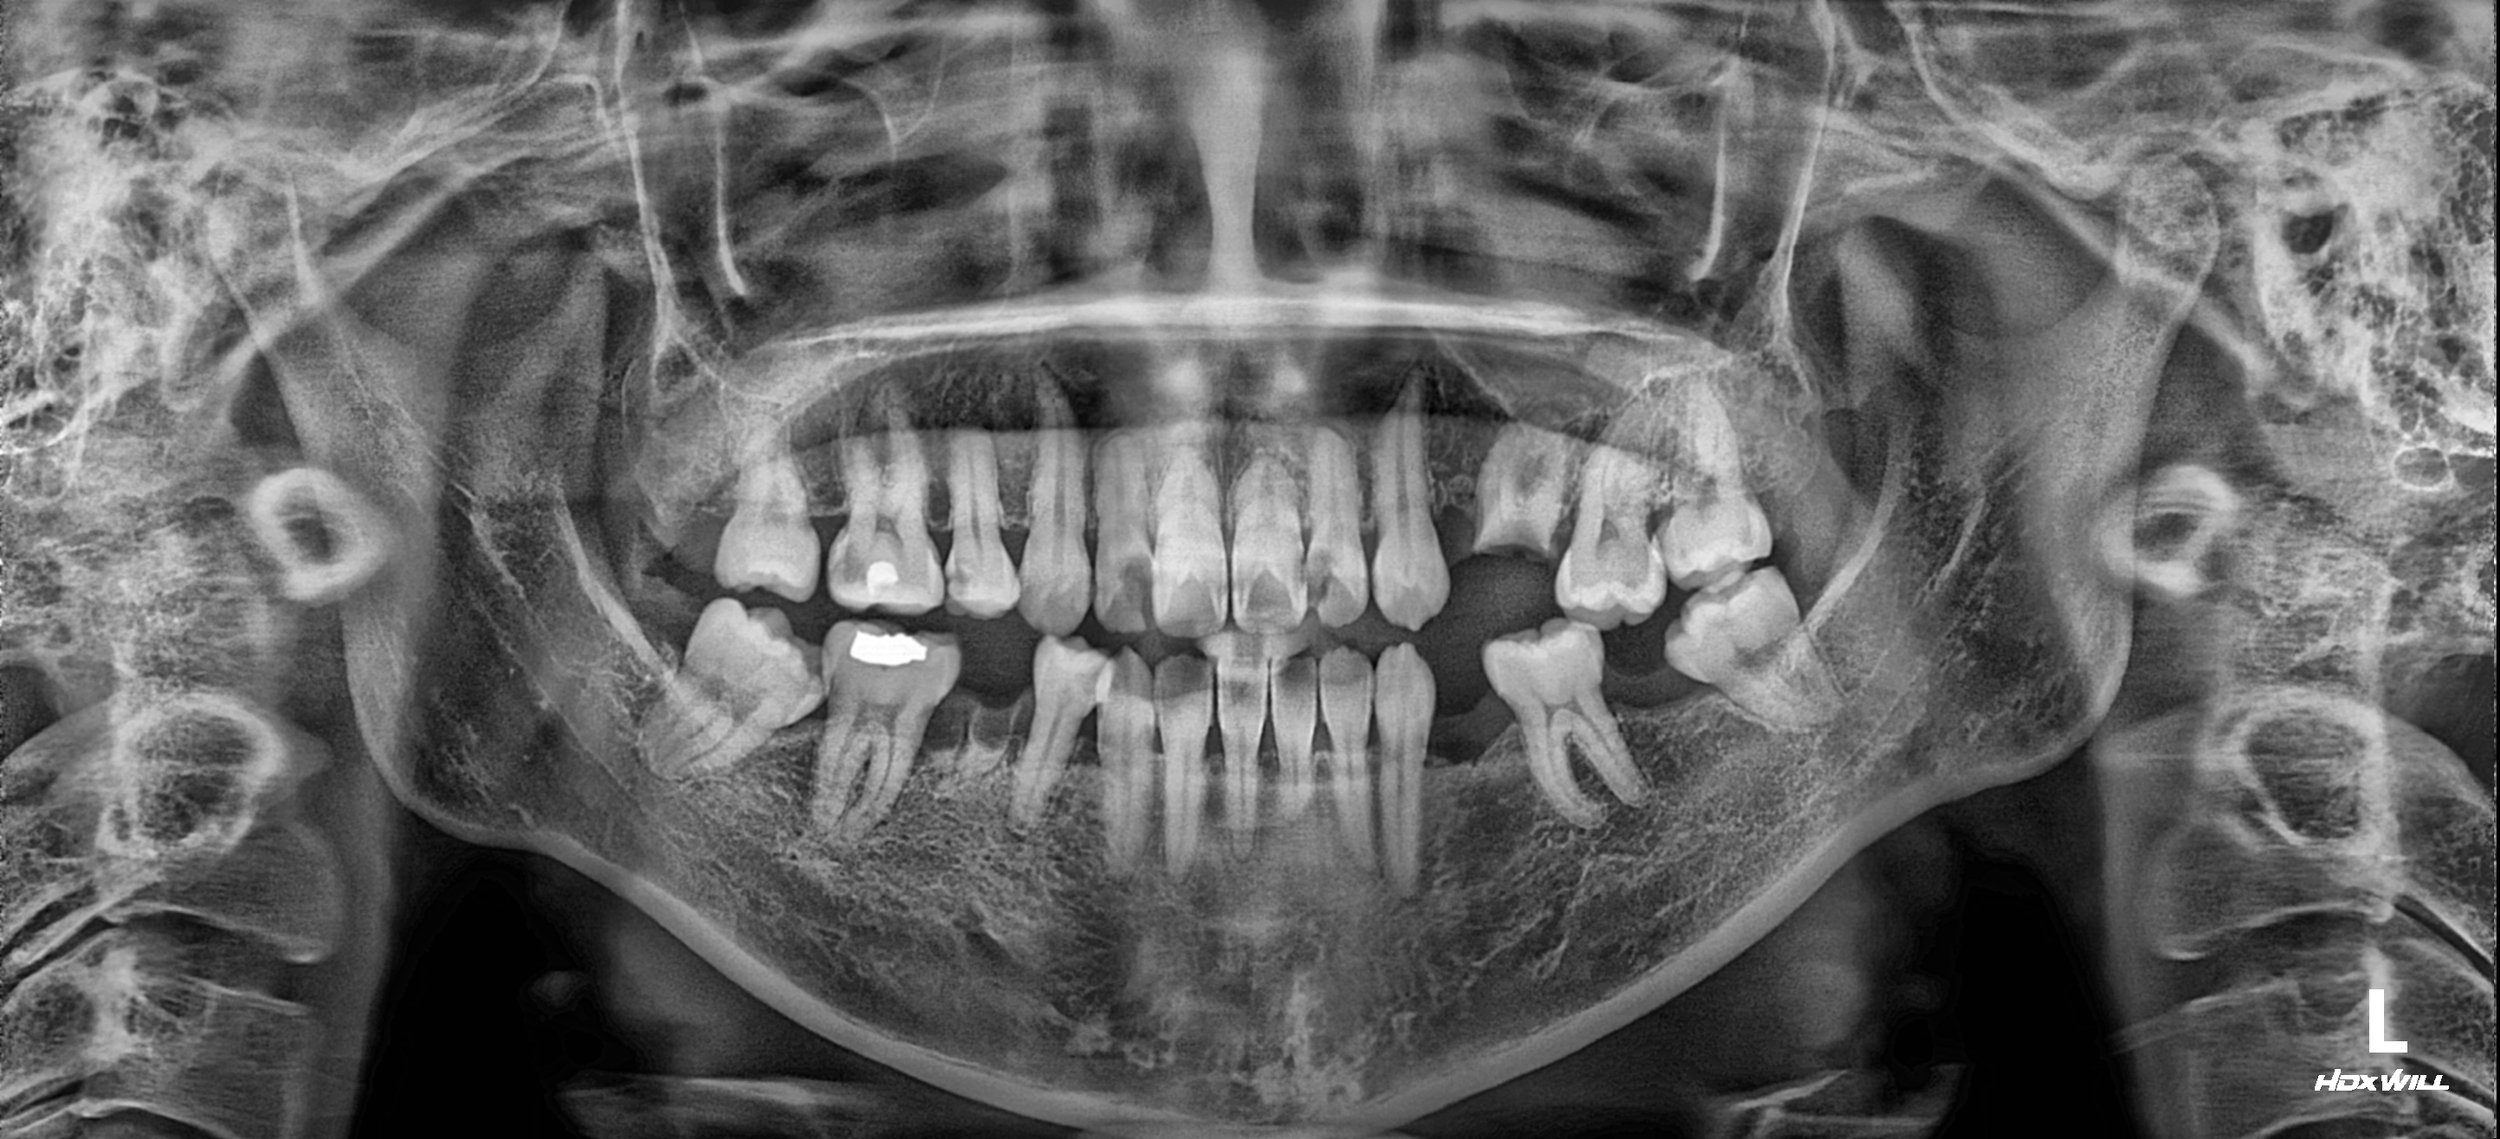

• Pre-operative Radiograph (OPG) OPG reveals generalized rampant caries, multiple non-restorable roots, and missing posterior units.

OPG - BEFORE